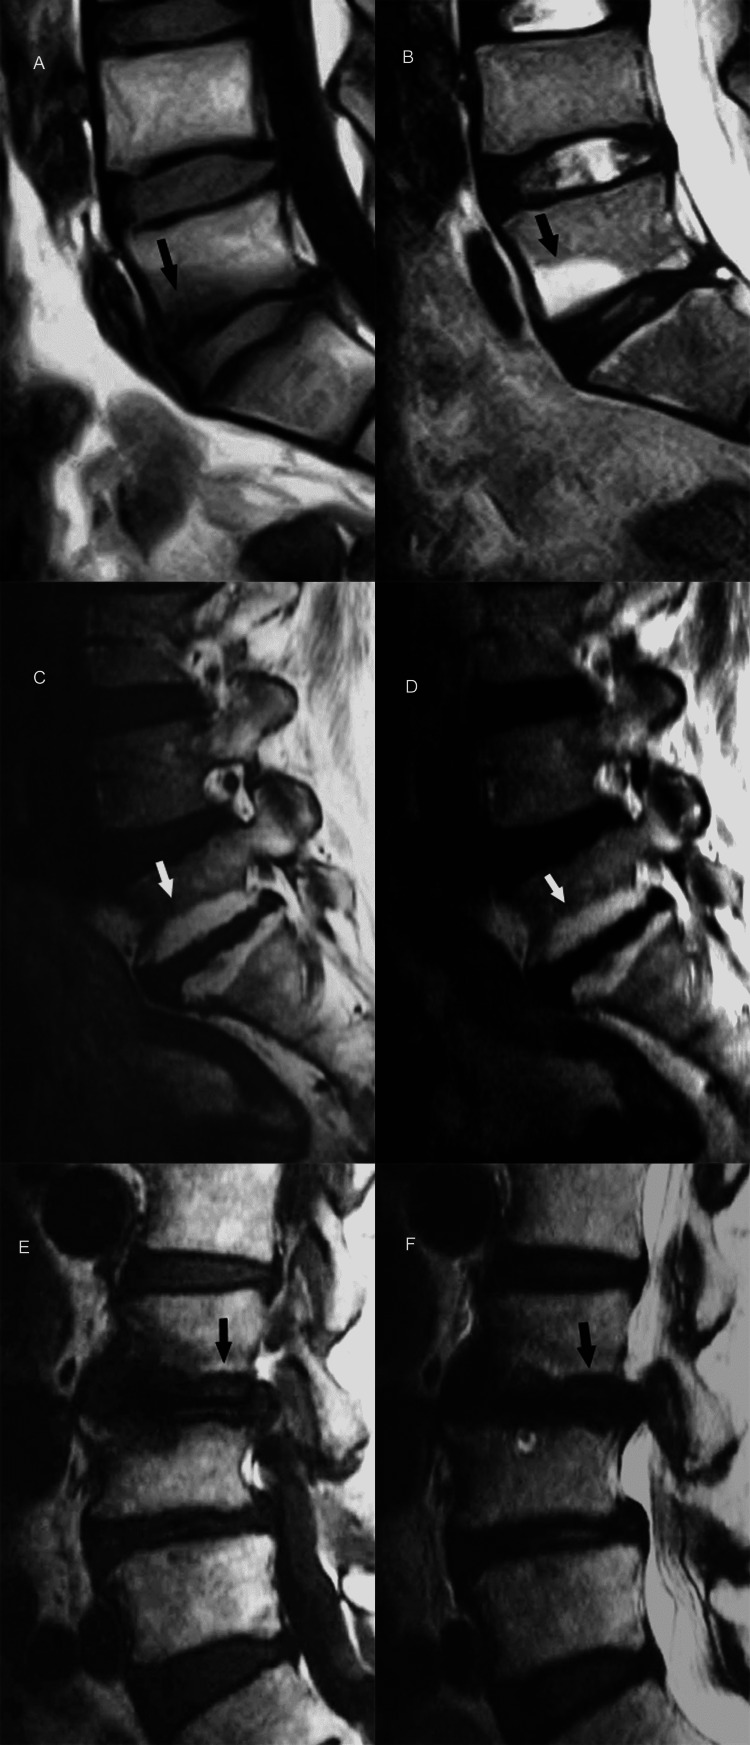

Progressive deterioration of the end-plates, cell senescence and microvascular insufficiency, especially when associated with osteoporosis, microtrauma or macrotrauma can result in marked weakening of the bony end-plate and fracture. Eventually, the vertebral body collapses [1,7]. With MR imaging, fracture is readily depicted as end-plate discontinuity with or without collapse (Figures 15A, 15B).

Figure 15. End-plate fracture.

(A) Sagittal T2-weighted MR image shows destruction of the lower end-plate of fourth lumbar vertebra (arrowhead) with abnormal high signal intensity in the lower part of vertebral body and intervening disc (arrow). Upper end-plate of fifth lumbar vertebral body appears unremarkable.

(B) Histology section reveals severe destruction of the bony and cartilaginous end-plate (arrowhead) at the site of fracture and adjacent disc fibrosis (arrow). Of note, the neighboring cartilaginous end-plate of fifth lumbar vertebral body is spared (asterisk).